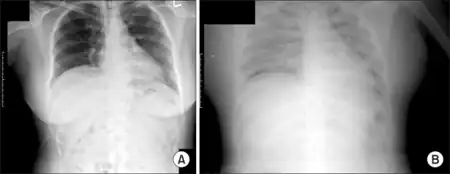

The second stage features the reabsorption of the initially extravasated fluid and albumin from the tissues, and it usually lasts 1 to 2 days. Intravascular fluid overload leads to polyuria and can cause flash pulmonary edema and cardiac arrest, with possibly fatal consequences.[2][3] Death from SCLS typically occurs during this recruitment phase because of pulmonary edema arising from excessive intravenous fluid administration during the earlier leak phase.[2][3] The severity of the problem depends on to the quantity of fluid supplied in the initial phase, the damage that may have been sustained by the kidneys, and the promptness with which diuretics are administered to help the patient discharge the accumulated fluids quickly.[2] A recent study of 59 acute episodes occurring in 37 hospitalized SCLS patients concluded that high-volume fluid therapy was independently associated with poorer clinical outcomes, and that the main complications of SCLS episodes were recovery-phase pulmonary edema (24%), cardiac arrhythmia (24%), compartment syndrome (20%), and acquired infections (19%).[4]